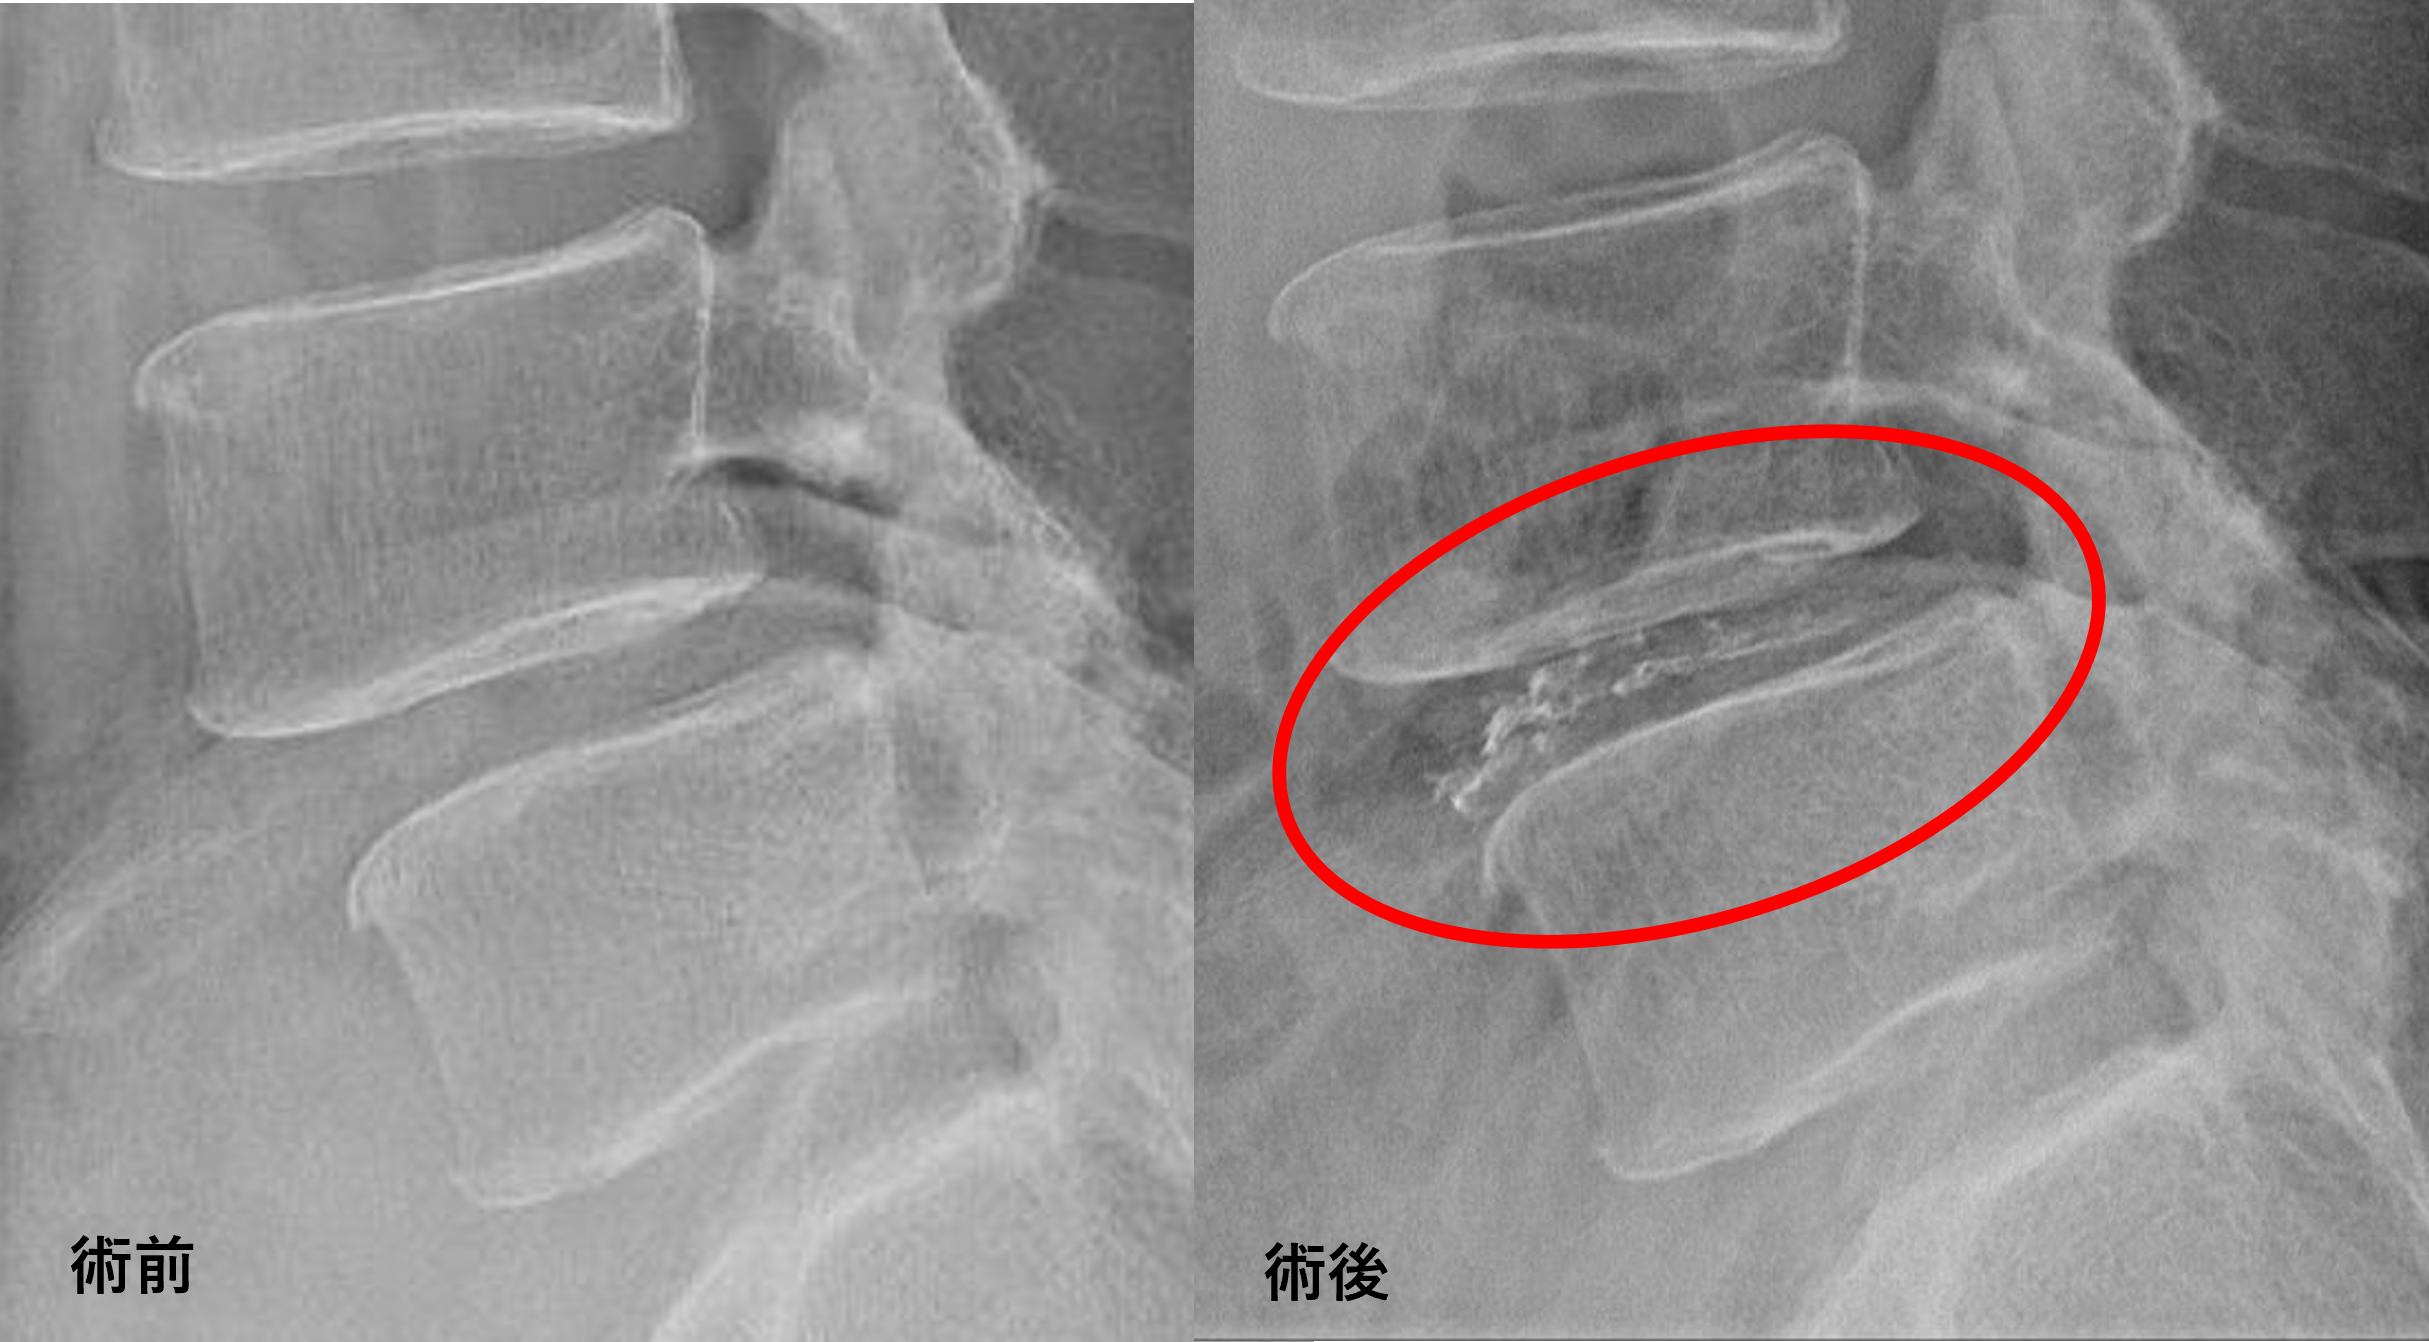

画像及び所見について

- L4/5 – 椎間板変性、膨隆、繊維輪断裂、変性すべり

以上のことが画像上認められました。

L4/5の椎間板所見による脊柱管の圧排が、症状の原因の可能性が高い。

患者様と相談の元、L4/5にセルゲル法を施行